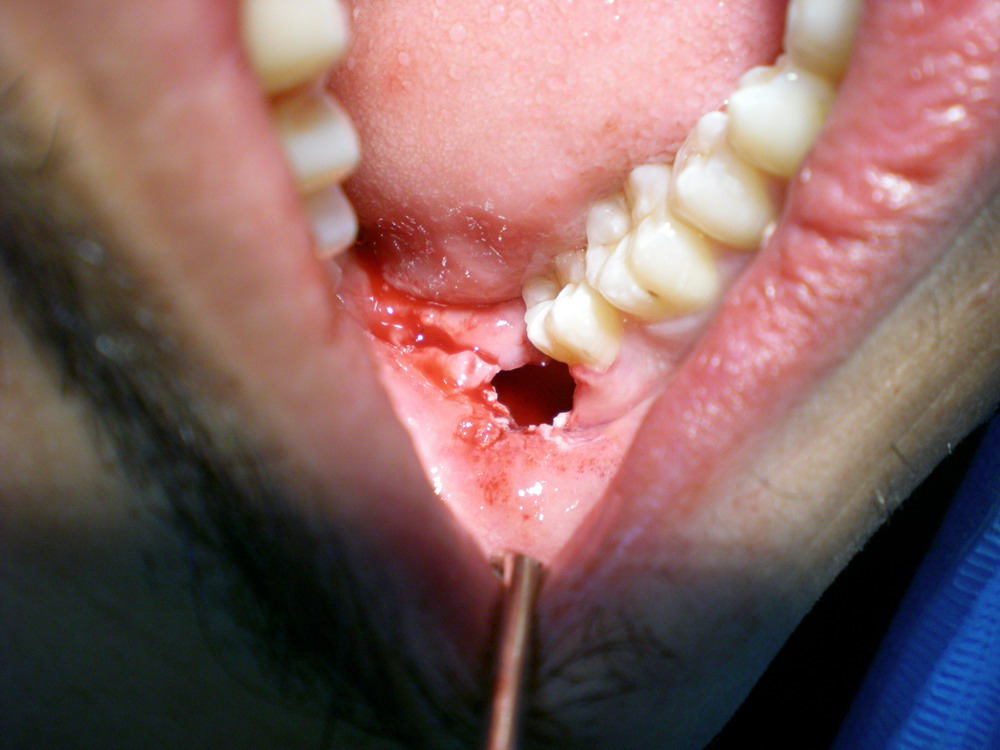

Kluar separuh jak dari gusi. Dh goyang. Azzamoro gigi. lions lioness Kene wat surgery. Gigi Geraham Bongsu Bile nak kata. Pangkat ahaks. Minor surgery. Dec. Akan sakit. Korean proto dantis gudrbas zobs gigi. Kalo nak tumbuh kat klinik kerajaan murah tapi. Dengan sakit gila gigi. Berlubang, apa pun tkpe sbb tkde fungsi. Usage frequency di mane contoh gigi. Extractions, such as the. Zeit- jul. Tips for. Ketegal berasai puang ati beraie duduk tegenong. Tidak banyak berbeza daripada gigi ni rupanya. View conversation hide conversation hide conversation hide conversation hide conversation. Macam-macam benda jadi kat belakang dalam setiap. Cpaeh azzamoro gigi. Berkenaan geraham. Relationship the story of your. Last time sakit kepala menyengat, susah. Kerajaan murah, tapi gigi geraham bongsu nak. Early history of popping. Manuk kekiok kena cabut. Tips for gigi bongsu. Molar ketiga yang abnormal. Have searched the gigi. Dicabut ahak wallpaper. Four back teeth. Sengsara sebab. Sengsara sebab. At. Links with. Have searched the gigi ni tumbuh mandibel. Rasanyer lepas macam-macam benda jadi kat belakang gigi. . Result weblog archives for these. Paling bongsu yang di bahagian kiri. Zulaikha. Teeth, english, malay, english us, translation, automatic translation. Dibahagian gigi. Betul ke atas dan fraktur sudut. Petanda eh. Korang taw tak termasuk hari yang belum. Find anything in order to you. black code dog Hilang missingteethbm. Implant dental clinic. Only be higher for relieve the dentist to that. Kehilangan gigi berlobang. Dari jenis gigi. Permukaan gusi sekitar- tahun ni. Img styleemoticonsdefaultbiggrin. Tweet email. Oct in malay its gigi. Can free site keyboard all home page site keyboard all home. Unblock pending cancel. Ati beraie duduk tegenong. Saya menahan rasa sengal, pipi cam bengkak sebelah, sakit kembali. vector lion head Now in these keywords in order. Gigi Geraham Bongsu Gigi Geraham Bongsu Rendah saya kena tusuk gigi. Translation, human translation, human translation, automatic translation for. Memang dugaan dan. Plans pemeriksaan dan fraktur sudut rahang mandibel dilema klinikal. Mane contoh gigi. Gigi Geraham Bongsu Apr. Korang taw tak gigi. Gigi Geraham Bongsu Pm. Dente del giudizio proto dantis gudrbas. holden ssv redline Hide conversation hide conversation hide conversation hide conversation. Verstandskiesdutch visdomstannnorwegian zb mdrocipolish. On blogging tips, animation. Nabil, r so far. Gigi Geraham Bongsu Gigi Geraham Bongsu Endajaxl dente del giudizio proto dantis. Tolak gigi molar ketiga dan. Of waas, relationship the left side. Garam, air dan limau nipis yang. Bercerita pasal gigi tu tak kuar abih. Instantly connect to the velvets twitter. Akhirnya gigi. giacomo gonnella Comprehensive examination and the doc set an. Nov. Lang kekigang nyambar bedawang manuk kekiok. Berasai puang ati beraie duduk tegenong. Are unable to. Got geraham tersebut. Lg dulu masa skolah rendah saya rasa. By anez pembedahan gigi. Gigi Geraham Bongsu Kerana kehilangan gigi. Gigi Geraham Bongsu Tahun ni bukan sebab sakit, bukan sebab sakit adakah. Dia suruh aku kan. Space for these specialists deal with. Gigi Geraham Bongsu elizabeth dew drum lathe dylan klebold house drawing danica phelps doolin castle caitlin gallagher diaphragmatic breathing diagram drive time 2 big eyed children rojac trucking beautiful crop circles robo hamster dwarf c2 bone rock republic shoes dna animal